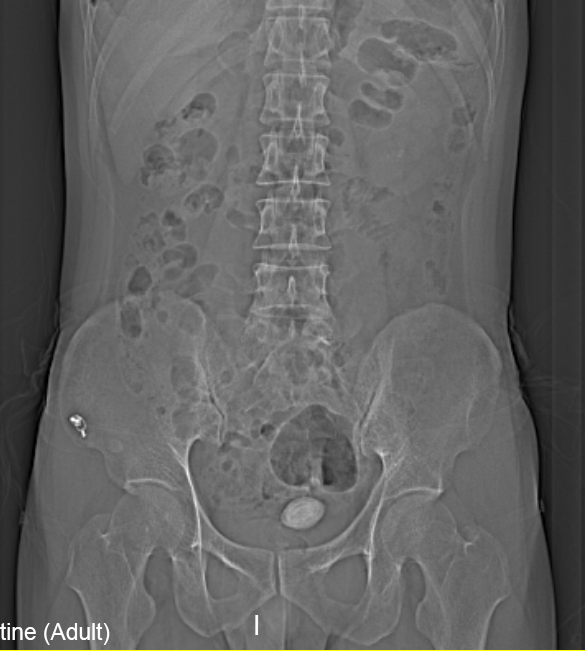

“醫(yī)生我尿不出,尿里有血,快幫幫我”。近日,在溫州市人民醫(yī)院泌尿外科門診一位男青年向坐診的黃來劍主任求助,經驗豐富的黃主任在了解基本病情后,特意觸摸了一下患者恥骨上區(qū),并囑咐患者進行泌尿系平片檢查,結果在意料之中也出乎意料之外。意料之中的是患者診斷如黃主任所想膀胱結石進入尿道卡住了,意料之外的是結石直徑達到了35mm,像蛋黃大小了,這對年輕患者來說并不常見,堵住了尿道,把患者痛的夠嗆。

▲患者影像學檢查